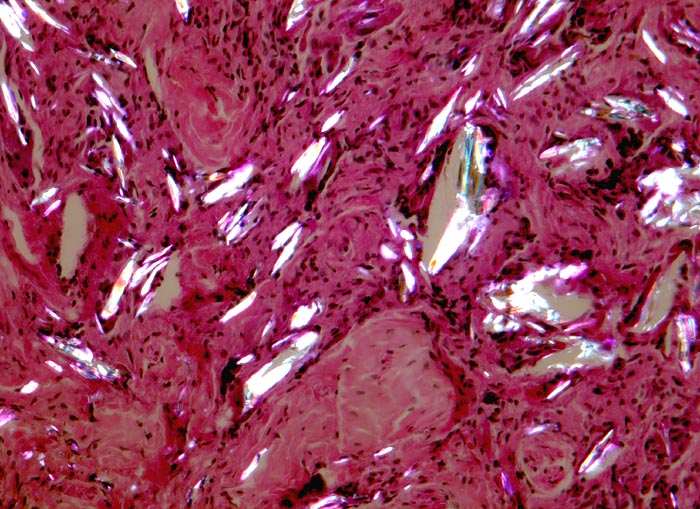

Morphologische Merkmale:

• Knotige Granulome umgeben von wenig Skelettmuskulatur.

• Granulombildung aus Histiozyten und mehrkernigen Riesenzellen vom Fremdkörpertyp.

• Im Zytoplasma der Riesenzellen findet sich phagozytiertes exogenes Fremdmaterial.

• In den helleren Arealen des Granuloms liegen grössere Ansammlungen von Fremdmaterial extrazellulär.